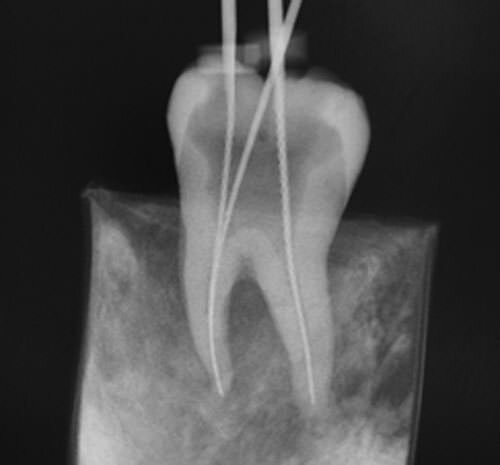

• Generalización de Rayos X

Generalización de Rayos X

Generalización del uso de los Rx en la profesión a partir de 1920 hace que la Endodoncia tenga un valor científico y se demuestra el valor de la conservación de los dientes.